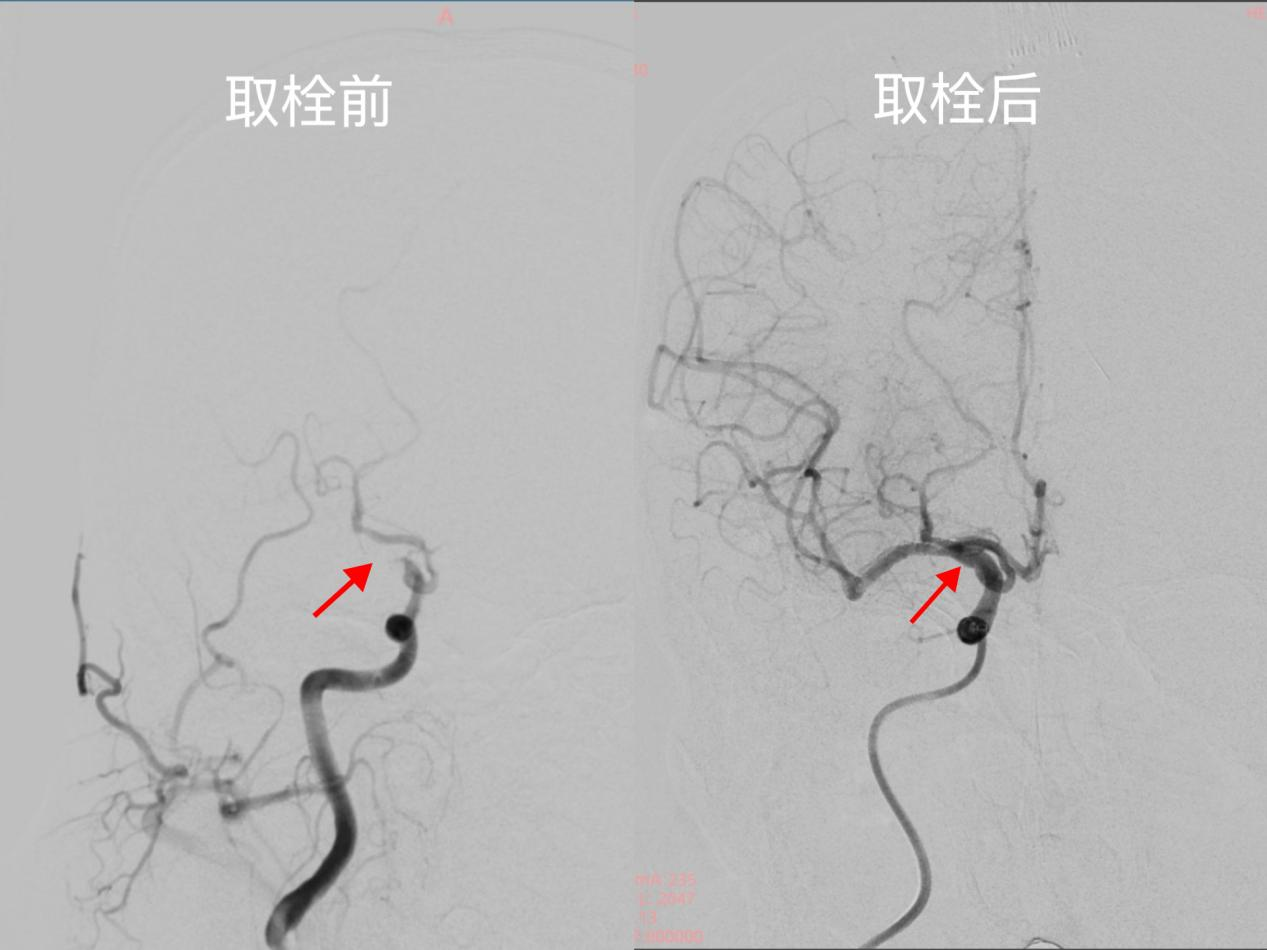

取栓前后造影结果对比

本例救治中,神经内科团队采用指南推荐的“桥接治疗”方案,一是静脉溶栓:快速溶解细小血栓,为脑组织争取生机;二是血管内机械取栓:针对大血管“堵点”,通过微导管精准取栓,立竿见影。

双技术联合应用,既避免瘫痪、失语等后遗症,更将血管再通率提升至90%以上,彰显我院在卒中超早期治疗中的硬核实力!